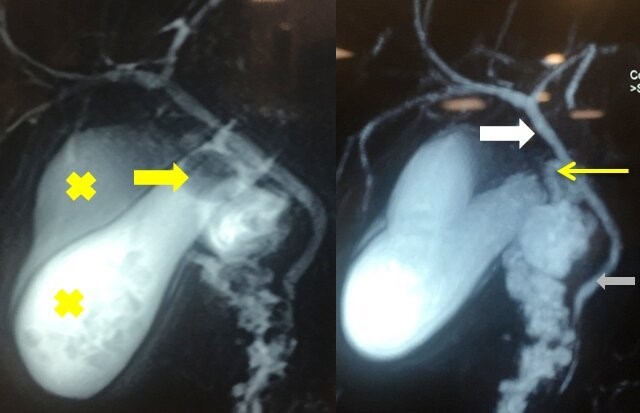

Con sospecha clínica de colecistitis aguda se solicitó paraclínica humoral, a destacar: leucocitosis leve, amilasemia y funcional y enzimograma hepático normales. La ecografía abdominal evidenció: dos cuerpos vesiculares, (ver imagen 1) con microlitiasis, uno de ellos con signos de colecistitis, sin dilatación de vía biliar intra ni extrahepática. Dado estos hallazgos, solicitamos para una valoración anatómica preoperatoria: colangiorresonancia (ver imagen 2) que confirmó la duplicación del cuerpo vesicular y la colecistitis en uno de ellos y no identificó otras malformaciones en vía biliar intra ni extrahepática.

Imagen 1: Ecografía abdominal, con corte axial y longitudinal de ambos cuerpos vesiculares, señalados con cruces (las mayores representan el cuerpo con signos de colecistitis).

Imagen 2: Colangiorresonancia magnética. Izquierda: evidencia ambos cuerpos vesiculares señalados con cruces, uno con litiasis incrustada en el bacinete (infundíbulo), flecha amarilla. Derecha: La flecha blanca señala el conducto hepático común. Se visualiza, además, el colédoco (flecha gris) y el cístico (flecha amarilla fina).